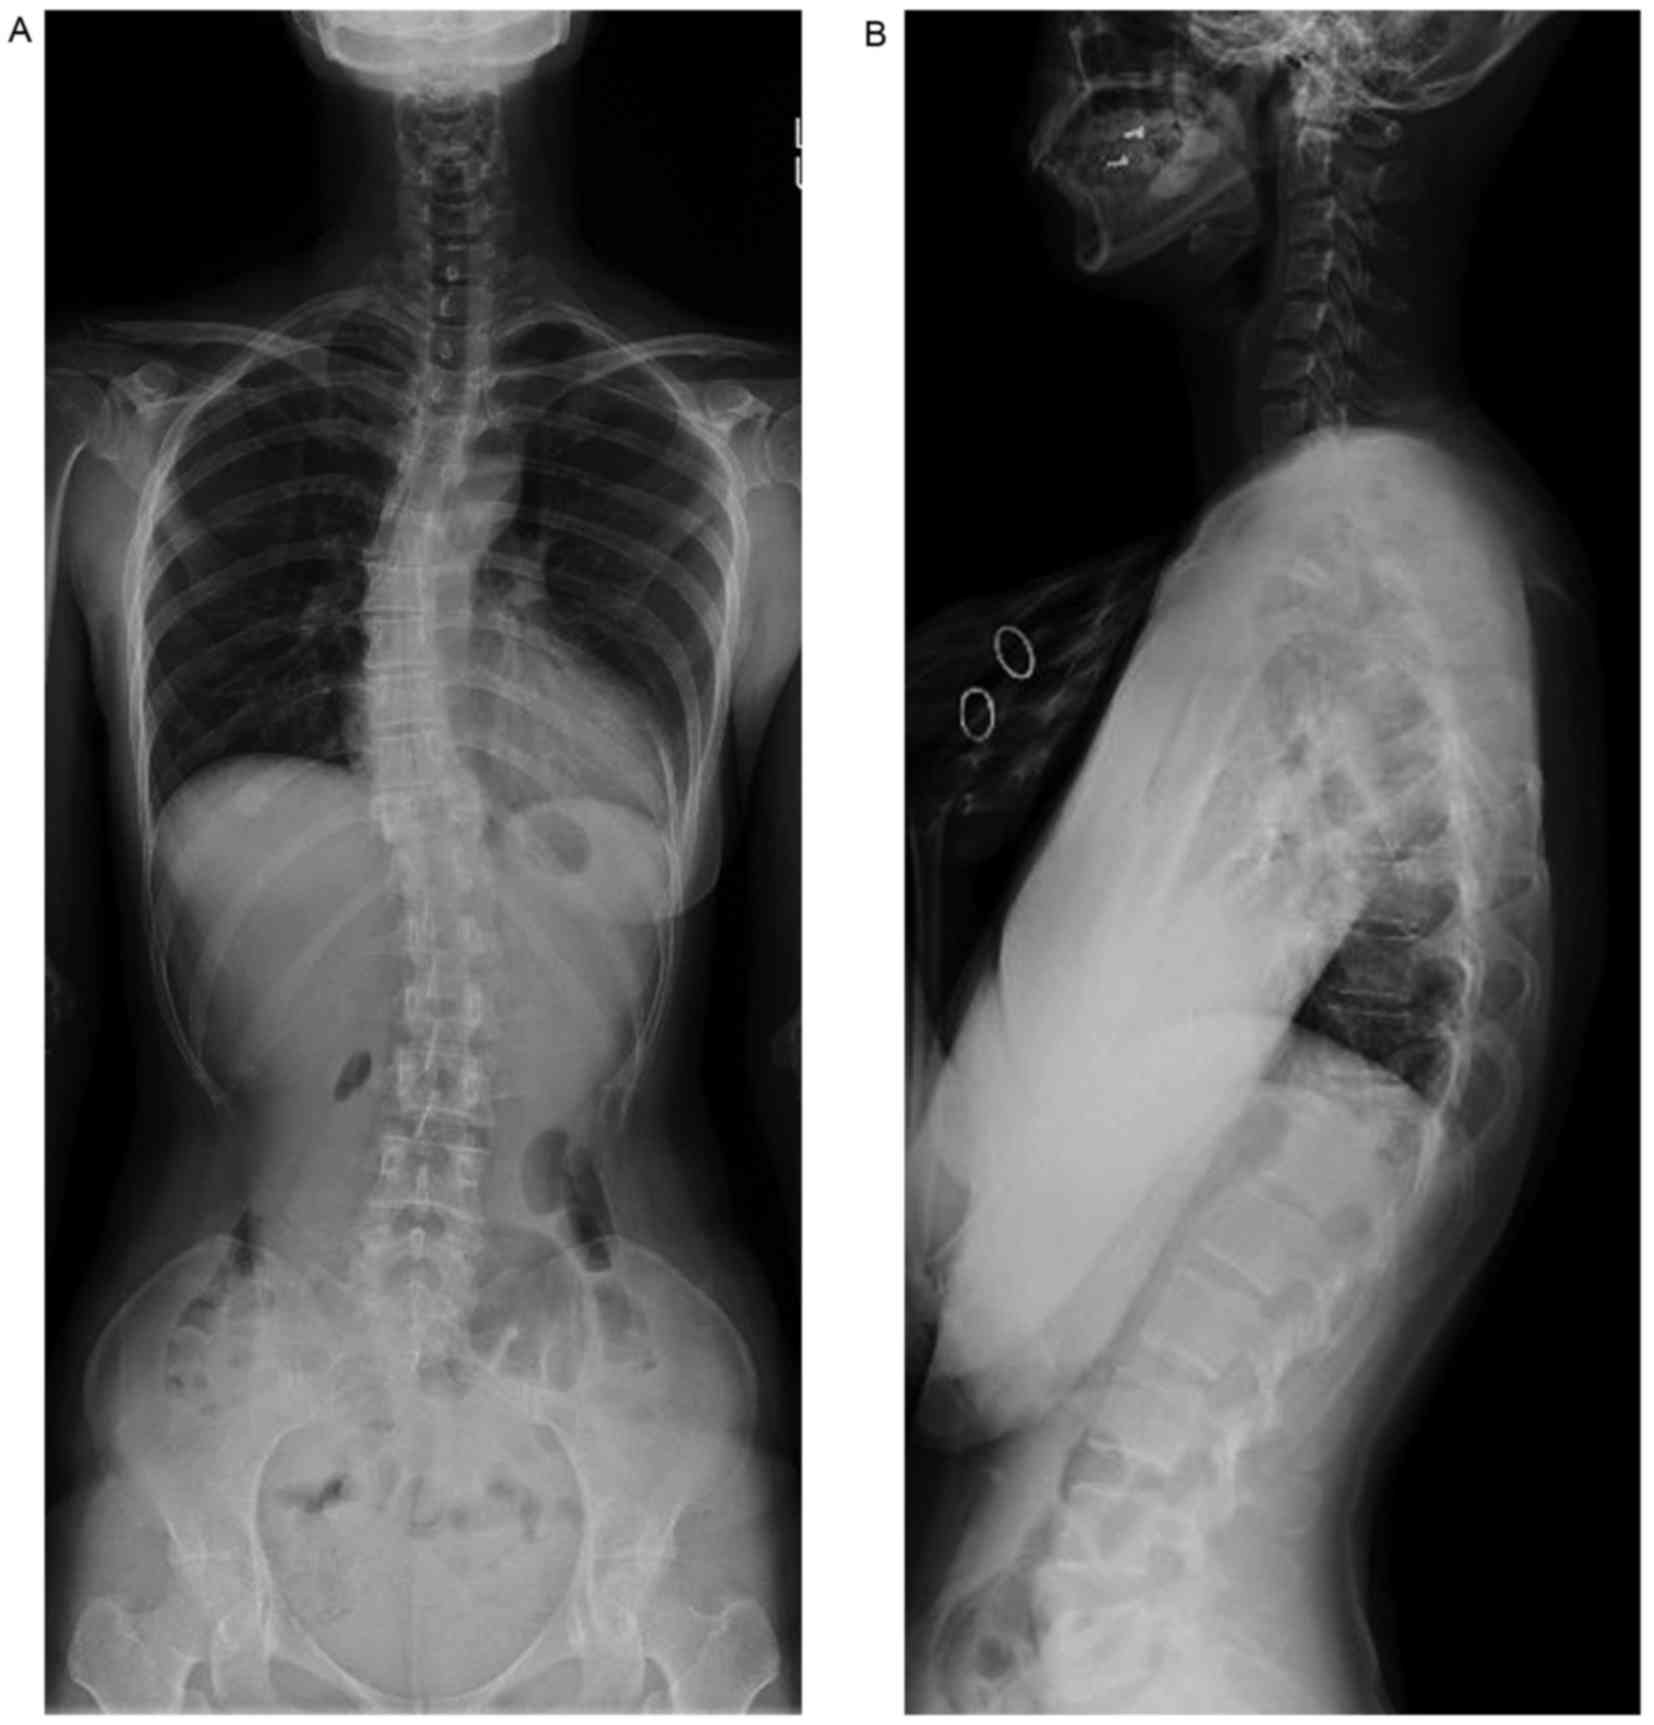

Measurement of vertebral body. For compression fracture vertebral body height loss vbhl and kyphotic angle ka are two important imaging parameters for determining the prognosis and appropriate treatment. Measurement of kyphosis and vertebral body height loss in traumatic spine fractures. A lateral computed tomographic ct reconstruction with measurements on the fourth lumbar vertebra in a 47 year old male subject vbhp vertebral body height posterior vbha vertebral body height. The human body has 33 vertebrae 24 of which make up the spine. The vertebral body corpus vertebra supports the weight of the trunk. All of the upper bodys weight bears down on the lumbar vertebrae leading to many back problems in this region despite the size and strength of the vertebrae.

Relations to age and to vertebral and iliac trabecular bone compressive strength bone. Epub 2016 aug 6. It is a thick bony structure which provides strength to the spine and protection for the spinal cord. This study used previous measurement methods to assess the degree of vbhl and ka compare and examine differences between various measurement methods and examine the correlation between relevant measurement parameters. It is generally cylindrical in shape but there is a wide range of variation for the shape and size in different regions and in different mammalian species. The sacral region of the spine contains only the sacrum a single bone in the adult skeleton that is formed by the fusion of 5 smaller vertebrae during adolescence.